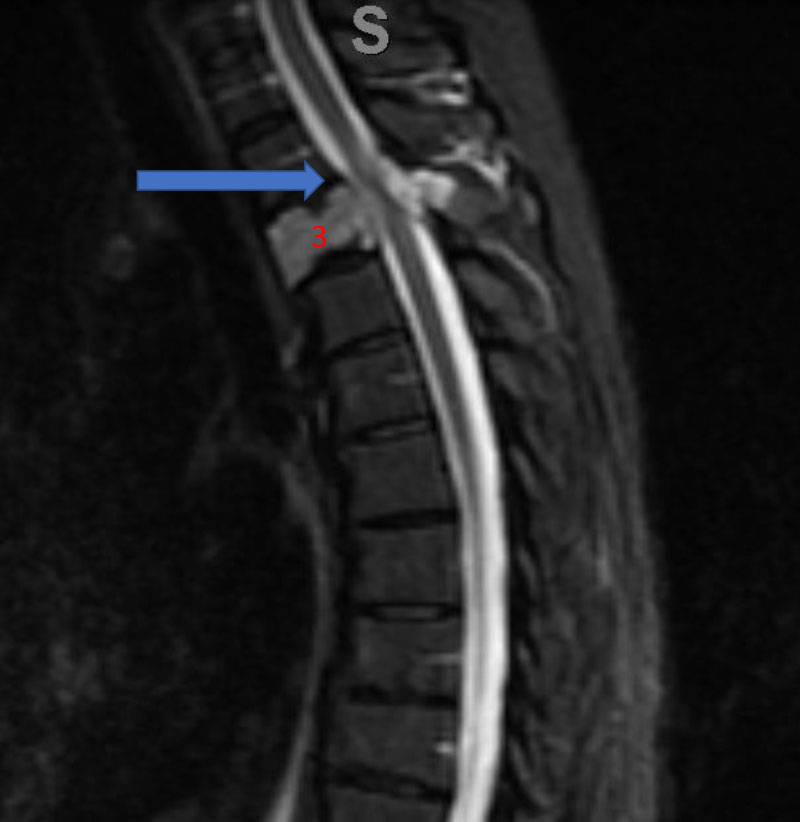

He presented to the emergency room with a one-week history of thoracic pain in addition to bilateral lower extremity weakness and paraparesis. MRI imaging with contrast showed a diffuse abnormal signal within the vertebral body of T3 and the posterior elements with lobulated soft tissue lesion extension into both paraspinal areas (Figure 1. A, B, C).

Figure 1. A) Sagittal T2 MRI demonstrates aggressive hyperintense T3 hemangioma involving the body and posterior elements compressing the thoracic spinal cord (arrows)

Figure 1. B and C) Axial MRI images of T3 demonstrates extensive infiltrative lesion with extradural compression of the thoracic spinal cord. (Dashed lines in A) tumor infiltration; Dashed lines and Arrows in B) cord compression.